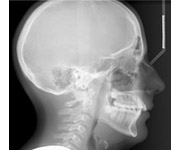

Residents gain experience in the treatment of patients with all types of dentofacial deformities. A broad mastery of alternative techniques with different variations of the Edgewise appliance is emphasized, along with modern forms of removable appliances. Treatment is provided for adults, adolescents, and children. Orthodontic residents also provide orthodontic treatment in complex rehabilitation cases in coordination with speciality residents in prosthodontics, periodontics, and pediatric dentistry. Surgical orthognathic cases are treated in conjunction with oral-maxillofacial surgery residents at the University of Maryland Medical System and the Johns Hopkins Univeristy Hospital.